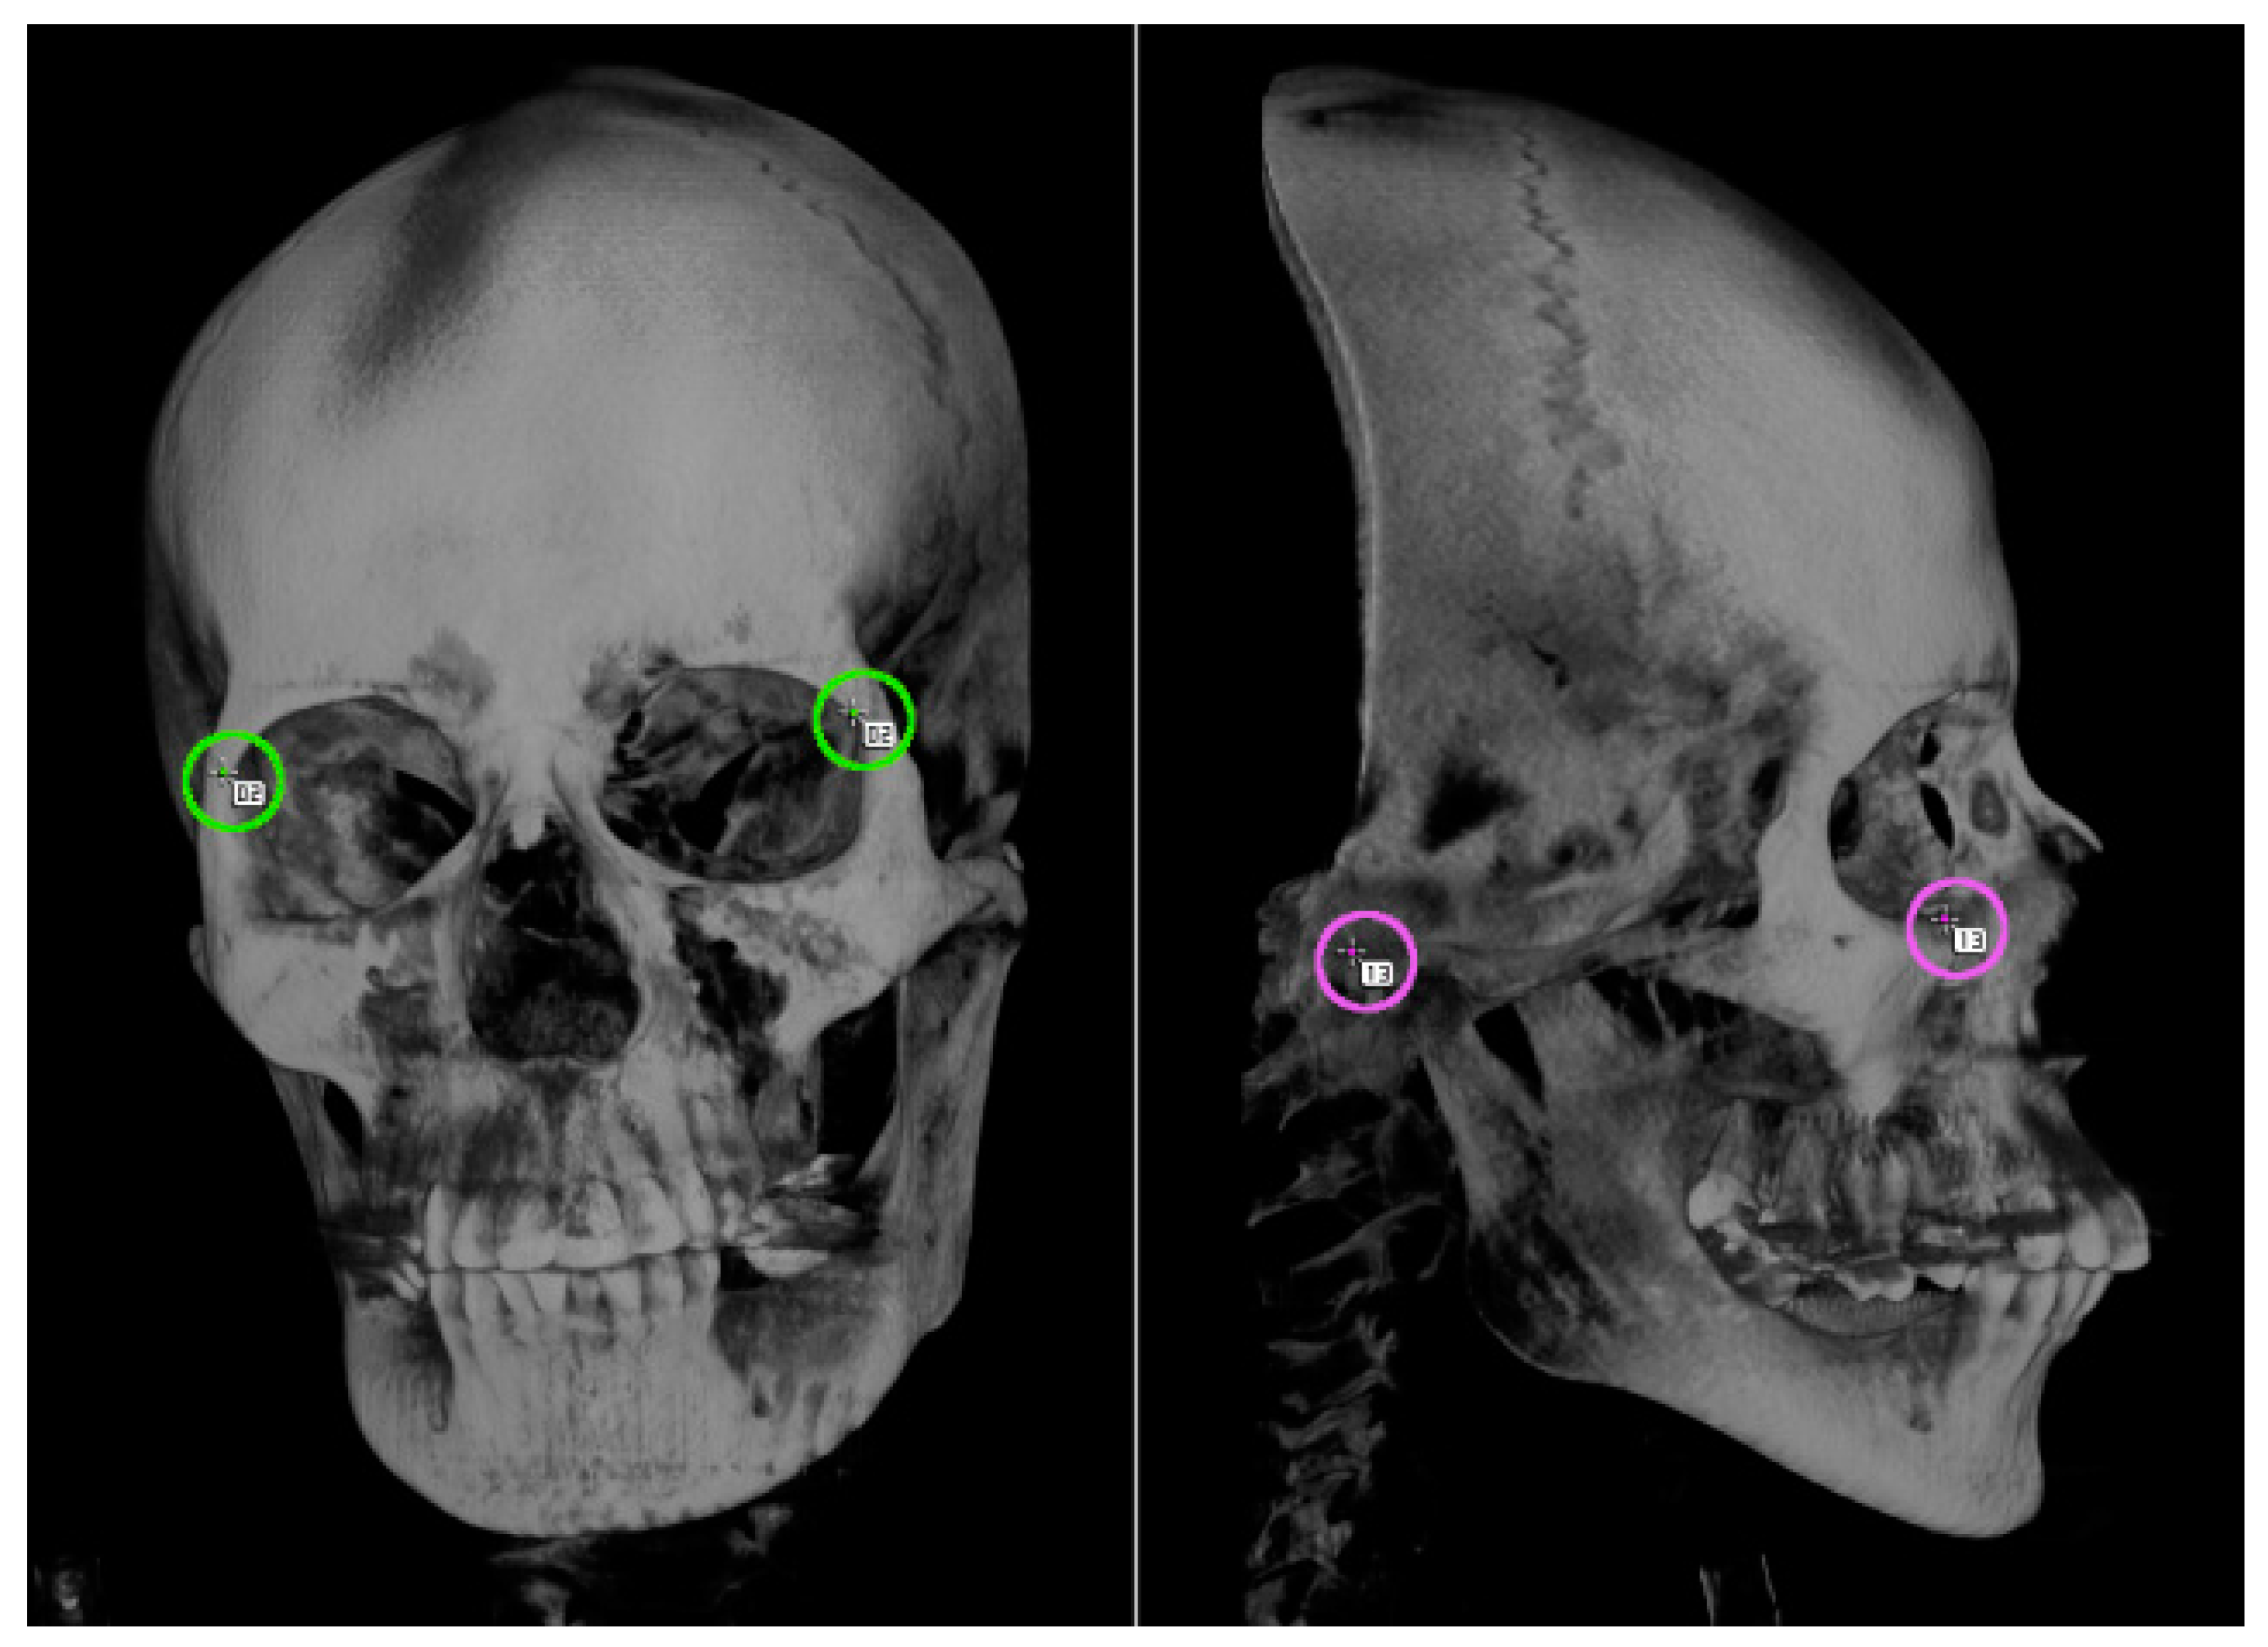

The craniofacial imaging data provided by doctors were not all straightforward. If the posture was inclined, the distances between the landmarks on the images would be compressed in the depth direction, which might result in inaccurate measurements. To prevent such compression, it was necessary to define the four landmarks for fixing the horizontal standard, to measure the two tilts of the axis, and to correct the inclinations of the imaging data before the actual measurements (Figure 4).

Figure 4. Four points used as a horizontal reference on the skeleton. Anterior image (left) and lateral image (right). To calculate the tilt of the skeleton with respect to the horizontal plane, images viewed from at least two directions are required.